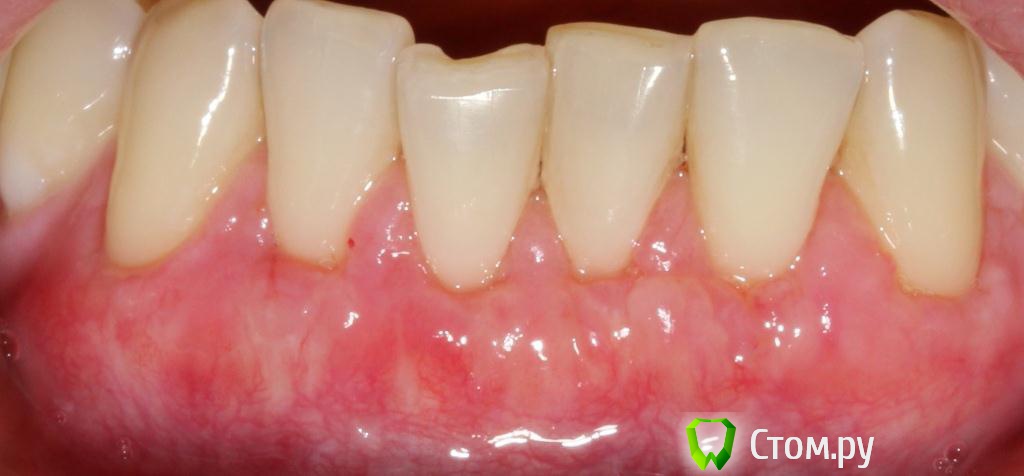

Популярный пост zzkz Опубликовано 18 сентября, 2014 Популярный пост Поделиться Опубликовано 18 сентября, 2014 (изменено) Жалобы эстетические и сильная чувствительность Рецессия от 34 до 44 Подготовка поверхности корней только скэйлинг СДТ с 2-х сторонНа небе каппа Ушивание пролен 6-0 2 недели после Чувствительности нет на сегондя. Ждать ли еще убыли или прироста? Сосочек закрыл "черный треугольник". Не уйдет ли? Изменено 18 сентября, 2014 пользователем zzkz 33 Ссылка на комментарий

kriokov Опубликовано 18 сентября, 2014 Поделиться Опубликовано 18 сентября, 2014 Ждать ли еще убыли или прироста? Сосочек закрыл "черный треугольник". Не уйдет ли? по шейкам мне кажется чуть выравняется. Про сосочки не знаю. Мне очень понравилась Ваша работа. 1 Ссылка на комментарий

Alexey Doc Опубликовано 18 сентября, 2014 Поделиться Опубликовано 18 сентября, 2014 по шейкам мне кажется чуть выравняется. +1 шейки выровняются.Сделайте реколл через 3 и 6 месяцев посмотрим как дозреет.Работа классная!! Ссылка на комментарий